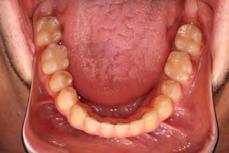

Clinical evaluation showed a mild Class III skeletal pattern with a constricted maxilla, mildly dolichofacial and straight

profile (Figure 1). Full adult dentition was present with all third molars extracted. Maxillary and mandibular incisors were normoclined. The maxillary midline coincided with the facial midline, and the mandibular midline was 2 mm to the right of the facial midline. There was a 2 mm to 5 mm lateral open bite on the right side from the second molar to the lateral incisor, and the maxillary occlusal plane was canted to the left of the interpupillary line. A lateral tongue thrust into the open bite was noted on swallow.

The right side was in posterior crossbite and there was an edge-to-edge anterior bite with wear on the maxillary central incisors. Mild gingival recession was noted, but soft tissue was generally within normal limits. CBCT analysis found no radiographic evidence of osteoarthritis in the TMJ joints, nor osseous or apical pathology involving the maxillary or mandibular teeth. His airway was not constricted. Initial report from the myofunctional therapist indicated that the patient never developed a mature swallow sequence and had a bilateral posterior tongue thrust.

Figure 1. Initial records.